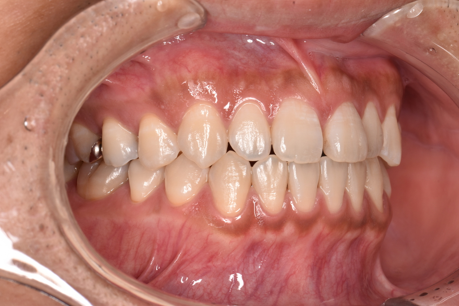

治療後

| 術後の経過・現在の様子 | 予定通りに治療が完了しました。 患者様にも「思っていたより痛みもなく、綺麗に並んで嬉しい」とご満足いただけました。 |